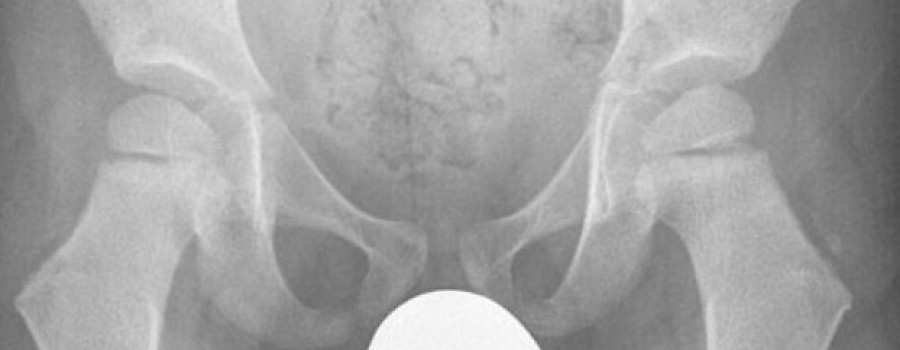

Das menschliche Skelett besteht aus gut 200 Knochen (individuell verschieden zwischen 206 und 214). Zusätzlich gibt es eine Reihe von Knochen und Varietäten, die nur bei einem kleinen Teil der Bevölkerung auftreten.